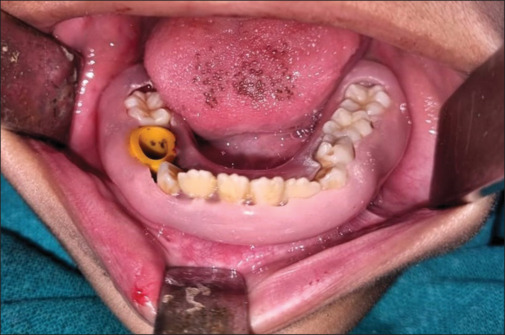

Special care is required for the management of jaw lesions in pediatric population. The following article describes the decompression technique as the least aggressive approach for the management of pediatric mandibular odontogenic keratocyst. A custom-made acrylic splint was fabricated around teeth, and it was attached to a piece of Foley's catheter to be used as a decompression port. Subsequent radiographs revealed a decrease in the size of radiolucency, bone formation, and eruption of permanent premolars during a time period of 1 year only. This technique prevents damage to permanent tooth buds, vital anatomic structures like inferior alveolar neurovascular bundle, and fracture of bone which may occur with other common techniques of management of odontogenic keratocyst.